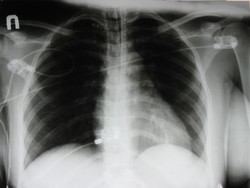

5 Tips Mencegah Kanker Paru

Kanker paru merupakan jenis kanker yang cukup mematikan, tapi bukan berarti tidak bisa dicegah. Untuk mencegahnya, yuk lakukan lima hal ini.